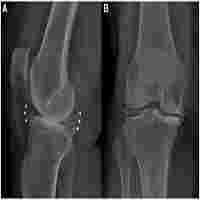

| Abstract | Osteophyte is an additional bony growth on a normal bone surface limiting or stopping motion at a deteriorating joint. Detection and quantification of osteophytes from computed tomography (CT) images is helpful in assessing disease status as well as treatment and surgery planning. However, it is difficult to distinguish between osteophytes and healthy bones using simple thresholding or edge/texture features due to the similarity of their material composition. In this paper, we present a new method primarily based on the active shape model (ASM) to solve this problem and evaluate its application to the anterior cruciate ligament transaction (ACLT) rabbit femur model via micro-CT imaging. The common idea behind most ASM-based segmentation methods is to first build a parametric shape model from a training dataset and then apply the model to find a shape instance in a target image. A common challenge with such approaches is that a diseased bone shape is significantly altered at regions with osteophyte deposition misguiding an ASM method and eventually leading to suboptimum segmentations. This difficulty is overcome using a new partial-ASM method that uses bone shape over healthy regions and extrapolates it over the diseased region according to the underlying shape model. Finally, osteophytes are segmented by subtracting partial-ASM-derived shape from the overall diseased shape. Also, a new semiautomatic method is presented in this paper for efficiently building a 3-D shape model for an anatomic region using manual reference of a few anatomically defined fiducial landmarks that are highly reproducible on individuals. Accuracy of the method has been examined on simulated phantoms while reproducibility and sensitivity have been evaluated on micro-CT images of 2-, 4- and 8-week post-ACLT and sham-treated rabbit femurs. Experimental results have shown that the method is highly accurate (R\bm 2=0.99), reproducible (ICC = 0.97), and sensitive in detecting disease progression (p values: 0.065, 0.001, and <;0.001 for 2 weeks versus 4 weeks, 4 weeks versus 8 weeks, and 2 weeks versus 8 weeks, respectively). |